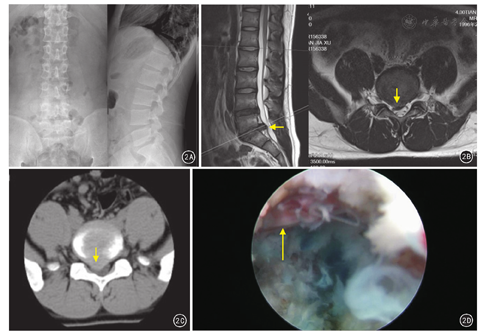

采用德国Joimax椎间孔镜手术系统。患者侧卧位,C形臂X线机确定病变椎间隙的体表投影,取L5/S1椎间盘水平线上、脊柱后正中线旁开10~12 cm为进针点,1%利多卡因分层浸润麻醉。穿刺定位针刺入L5上关节突外侧缘处,沿穿刺针插入套管,将工作套管插入椎管内、硬膜囊前、纤维环外。置入椎间孔镜,髓核钳摘除突出髓核组织。低温等离子系统射频止血、髓核消融,松解神经根周围粘连组织、纤维环成形。见图2。